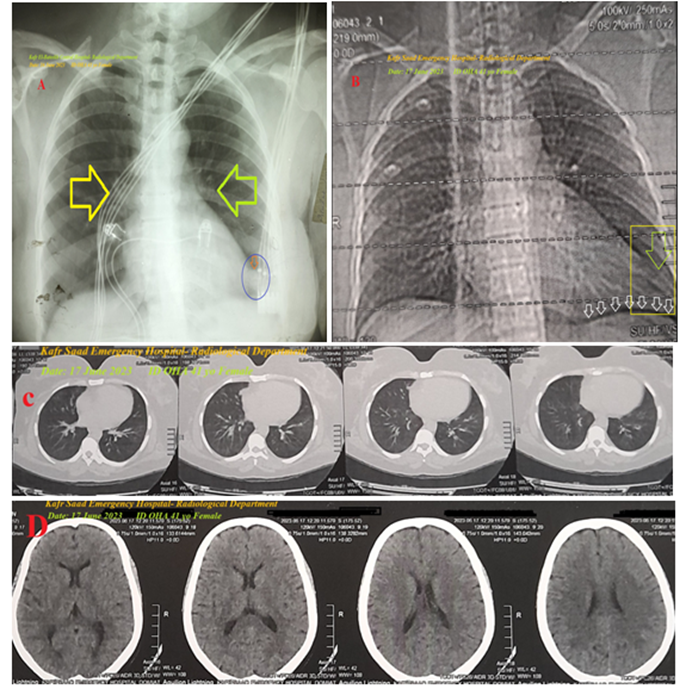

A 41-year-old married female housewife, patient, was presented to the intensive care unit (ICU) with palpitations, acute non-specific chest pain, and dizziness. Cough, headaches, and generalized body pain were associated symptoms. The patient has a history of diabetes mellitus 12 years ago, on long-acting insulin. She also has a history of bronchial asthma 20 years ago on intermittent anti-asthmatic medications. Upon general physical examination, the patient had tachypnea and distressed respiration, with a regular pulse rate (junctional tachycardia (JT) with VR of 165), blood pressure (BP) of 110/80 mmHg, respiratory rate of 25 bpm, a temperature of 36°C, and a pulse oximeter of oxygen (O2) saturation of 97%. No more relevant clinical data were noted during the clinical examination. The patient refused the referral for admission to the intensive care unit (ICU). He was initially managed at the ICU, with a junctional tachycardia, diabetes, non-specific chest pain, and Brugada syndrome. Initially, the patient was treated with O2 inhalation via an oxygen system line (100%, using a normal mask, 5L/min). The initial ECG tracing was performed on the initial presentation to the ICU, with one and a half calibration showing junctional tachycardia, normal axis, and coving-like ST-segment elevations in the aVR, V1, and V2 leads. There is a loose lead artifact in the V5 lead (Figure 1A). The second ECG tracing was taken within 3 minutes of the above ECG tracing, with one and a half calibration showing junctional tachycardia, interlacing of premature junctional complexes in V1 and V2 leads, with the same changes as above. But with AC artifacts and Wavy triple sign (Yasser's sign) in V6 lead (Figure 1B). The patient was treated with amiodarone IV bolus (300 mg IV over 20 minutes, then a continuous IVI at a rate of 1 mg/min for 6 hours). The patient was monitored hourly for vital signs and O2 saturation. The third ECG tracing was taken within 22 hours of the above ECG tracing, with one and a half calibration showing sinusoidal AF, normal axis, and disappearance of the above coving-like ST-segment elevations (Figure 1C). Amiodarone IV was given as a maintained dose, Diltiazem tablets (60mg, OD), SC Enoxaparin 40 mg, OD, and Warfarin tablet (5 mg, OD) were added. There is a new mild fever (temp of 38.5°C), tachypnea, dry cough, and frequent micturition. Urine analysis on the second day of ICU admission showed: pus over 50, RBCs: 10-12, and epithelial cells (++). The fourth ECG tracing was taken within 42 hours of the above ECG tracing, showing sinus tachycardia, normal axis, a coving-like ST-segment elevations in the aVR, V1, and V2 leads (Figure 1D). The fifth ECG tracing was taken within 6 hours of the above ECG tracing, showing sinus tachycardia, right axis deviation, with coving-like ST-segment elevations in I and aVL leads. There is a loose lead artifact in V2 lead (Figure 1E). Cefotaxime vials (1 gm IV BID) and paracetamol (500 mg TID as needed) were added. The sixth ECG tracing was taken within 1 minute of the above ECG tracing, showing sinusoidal AF, right axis deviation, with coving-like ST-segment elevations in the I and aVL leads. There is a loose lead artifact in V2 lead (Figure 1F). The seventh ECG tracing was taken within 1 minute of the above ECG tracing, showing sinusoidal AF, right axis deviation, with coving-like ST-segment elevations in I and aVL leads. There is a loose lead artifact in the V2 lead (Figure 1G). The eighth ECG tracing was taken within 24 hours of the above ECG tracing, showing sinusoidal AF, right axis deviation, with coving-like ST-segment elevations in the I and aVL leads. There is sagged ST-segment depression in the V4-6 leads (Figure 1H). The ninth ECG tracing was taken within 7 hours of the above ECG tracing, showing sinusoidal AF with normal axis (Figure 1I). The tenth ECG tracing was taken within 5 days of the above ECG tracing, with one and a half calibrations, showing junctional tachycardia, left axis deviation, with coving-like ST-segment elevations in the III, aVR, and V1 leads. There is a retrograde P wave in V6 lead (Figure 1J). The eleventh ECG tracing was taken within 8 hours of the above ECG tracing, showing sinusoidal AF, right axis deviation, with coving-like ST-segment elevations in I and aVL leads. There is equivocal QRS in the aVR lead (Figure 1K). The chest X-ray film PA view performed on the initial presentation to the ICU shows tail-like outward apical elongation. There are mild right and left consolidation opacities (Figure 2A). The plain film of chest CT performed on the initial presentation to the ICU showed tail-like outward apical elongation with a narrow lower black recess separating the left diaphragmatic surface and lower surface of the right heart (Figure 2B). Serial cuts of chest CT were done on the initial presentation to the ICU, showing no abnormalities (Figure 2C). Serial cuts of brain CT were done on the initial presentation to the ICU, showing no abnormalities (Figure 2D). The echocardiography was done within 4 days after the ICU presentation, showing tachycardia, mild mitral regurgitation, and a good LV systolic function of an EF of 53% (Figure 3). The initial laboratory: complete blood count (CBC); Hb was 11.3 g/dl, RBCs; 5.37*103/mm3, WBCs; 12.0*103/mm3 (Neutrophils; 53.7 %, Lymphocytes: 36.1%, Monocytes; 8.2%, Eosinophils; 0% and Basophils 0%), Platelets; 327*103/mm3. CRP was 6.0. SGPT was (26.7 U/L). Serum albumen was 4.2 gm/dl. Serum creatinine was (0.97 mg/dl). RBS was (254 mg/dl). D-dimer was 0.3ug/ml. ABG was done in the third day; (PH; 7.41, PCO2; 49.6 mmHg, HCO3; 31.8 mmHg, So2; 96%, and PaO2; 78 mmHg). INR was 1.04 with a prothrombin time of 13.08 seconds. The associated electrolytes in the ABG profile: Plasma sodium was 160 mmol/L. Serum potassium was (3.2 mmol/L). Serum ionized calcium was (1.01 mmol/L). The CBC was repeated in the third day; Hb was 11.2 g/dl, RBCs; 5.33*103/mm3, WBCs; 13.7*103/mm3 (Neutrophils; 67.6 %, Lymphocytes: 27.6%, Monocytes; 4.8%, Eosinophils; 0% and Basophils 0%), Platelets; 322*103/mm3. The troponin initial test was negative. On the ninth day; The CBC: Hb was 10.8 g/dl, RBCs; 5.17*103/mm3, WBCs; 13.8*103/mm3 (Neutrophils; 63.7 %, Lymphocytes: 31.4%, Monocytes; 4.9%, Eosinophils; 0% and Basophils 0%), Platelets; 210*103/mm3. CRP was 12.0. SGPT was (31.0 U/L). Serum creatinine was (0.6 mg/dl). Rheumatoid factor was negative. Migratory Brugada syndrome, variable interlacing arrhythmias, ECG axis deviations, and mild chest and urinary tract infections in a diabetic patient are the most probable diagnosis. Within eleven days of the above at-ICU management, the patient finally showed nearly complete clinical and ECG improvement. The patient was continued on Diltiazem tablets (60 mg, OD), Amiodarone tablets (200 mg, OD), Warfarin (5mg, OD), long-acting insulin, oral calcium, and Vitamin-D preparations for 14 days with further recommended cardiac and urological follow-up.

Figure 2A: Plain chest X-ray film, PA view was taken on the initial presentation to the ICU, showing tail-like outward apical elongation (dark blue circle and golden arrow). There are mild right (yellow arrow) and left (lime arrow) consolidation opacities. B. Plain film of chest CT was taken on the initial presentation to the ICU, showing tail-like outward apical elongation (yellow square and lime arrow) with a narrow lower black recess separating the left diaphragmatic surface and lower surface of the right heart (small white arrow). C. Serial cuts of chest CT, showing no abnormalities. D. Serial cuts of brain CT, showing no abnormalities.

Overview: A middle-aged married female housewife, patient, was presented to the ICU with junctional tachycardia, diabetes, non-specific chest pain, Brugada syndrome, and past bronchial asthma. The primary objective for my case study was the presence of a middle-aged married female housewife, patient, with junctional tachycardia, diabetes, non-specific chest pain, Brugada syndrome, and past bronchial asthma in the ICU. The secondary objective for my case study was the question of how to manage the case. Mild chest and urinary tract infections were associated with the condition (Figures 2A-2B). There were variable associated arrhythmias throughout the course of the ICU admission. It started with junctional tachycardia (Figures 1A-1B), then sinusoidal AF (Figure 1C), then sinus tachycardia (Figures 1D-1E), then sinusoidal AF (Figures 1F-1I), then junctional tachycardia (Figures 1J-1K). There were also different serial changes in axis deviations in the ECG in the course of the ICU admission. It started with normal axis (Figures 1A-1D), then right axis deviation (Figures 1E-1H), then normal axis (Figure 1I), then left axis deviation (Figure 1J), then right axis deviation (Figure 1K). Indeed, although there is no clear known cause for these different serial changes in axis deviations in the ECG, Amiodarone is suggested as the cause [17]. Naranjo's probability scale was used to assess the probable relationship between these different serial changes in axis deviations and the causative agent, Amiodarone. Naranjo's probability scale in the current case study was +8. It means that there was a probable relationship between the serial changes in axis deviations and the causative Amiodarone (Table 1).

There is no known mechanism for these migrations. Genetic migrations of Brugada syndrome may be a suggested theory. Plain chest X-ray film, PA view showing tail-like outward apical elongation with a narrow lower black recess separating the left diaphragmatic surface and lower surface of the right heart. This tail-like outward apical elongation is also newly described. In parallel to these axis deviations and transitions in coving-like ST-segment elevations from one specific lead to another specific ones are new description regarding Brugada syndrome is provided. It may be named as "Tail Apex Syndrome" (Figure 4). Acute pulmonary embolism is the most implicated differential diagnosis. The d-dimer against it. I can’t compare the current case with similar conditions. There are no similar or known cases with the same management for near comparison. The only limitation of the current study was the unavailability of genetic analysis for Brugada syndrome.